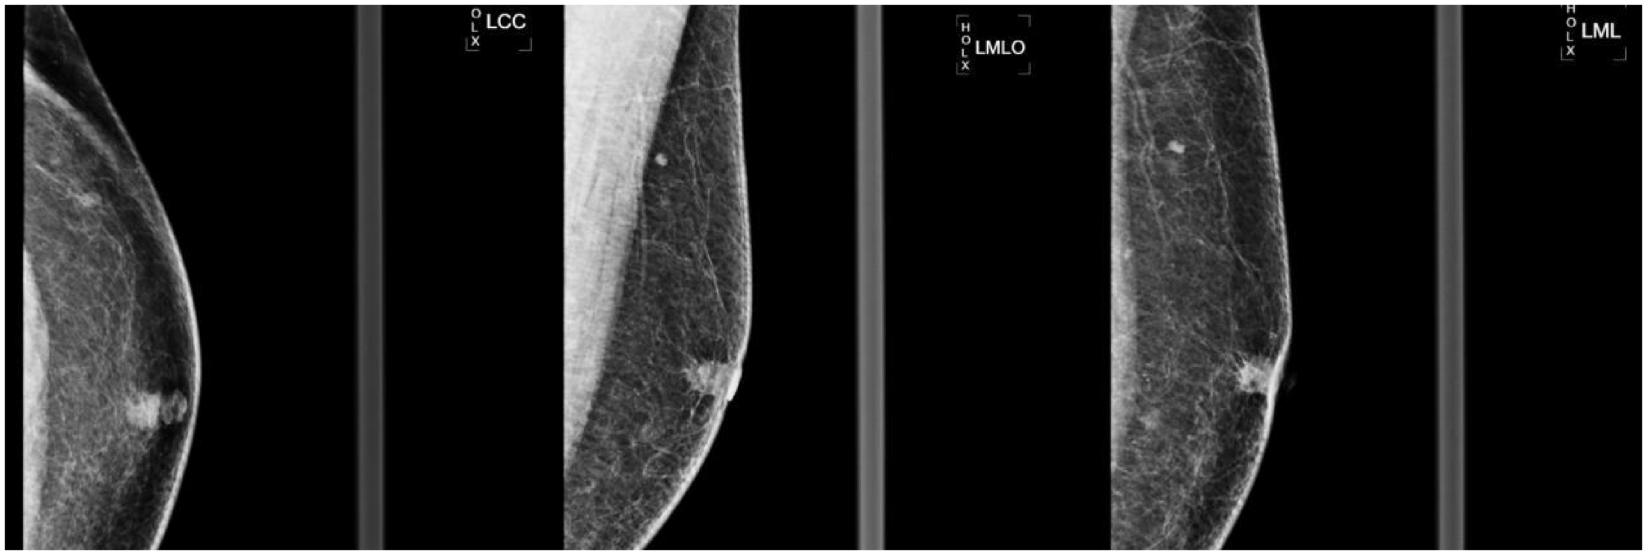

乳腺钼靶:左乳晕下可见 10×9mm 不规则高密度肿块,伴毛刺征、结构扭曲及乳头内陷,BI-RADS 5 类(图 2)。

图2 左乳腺钼靶